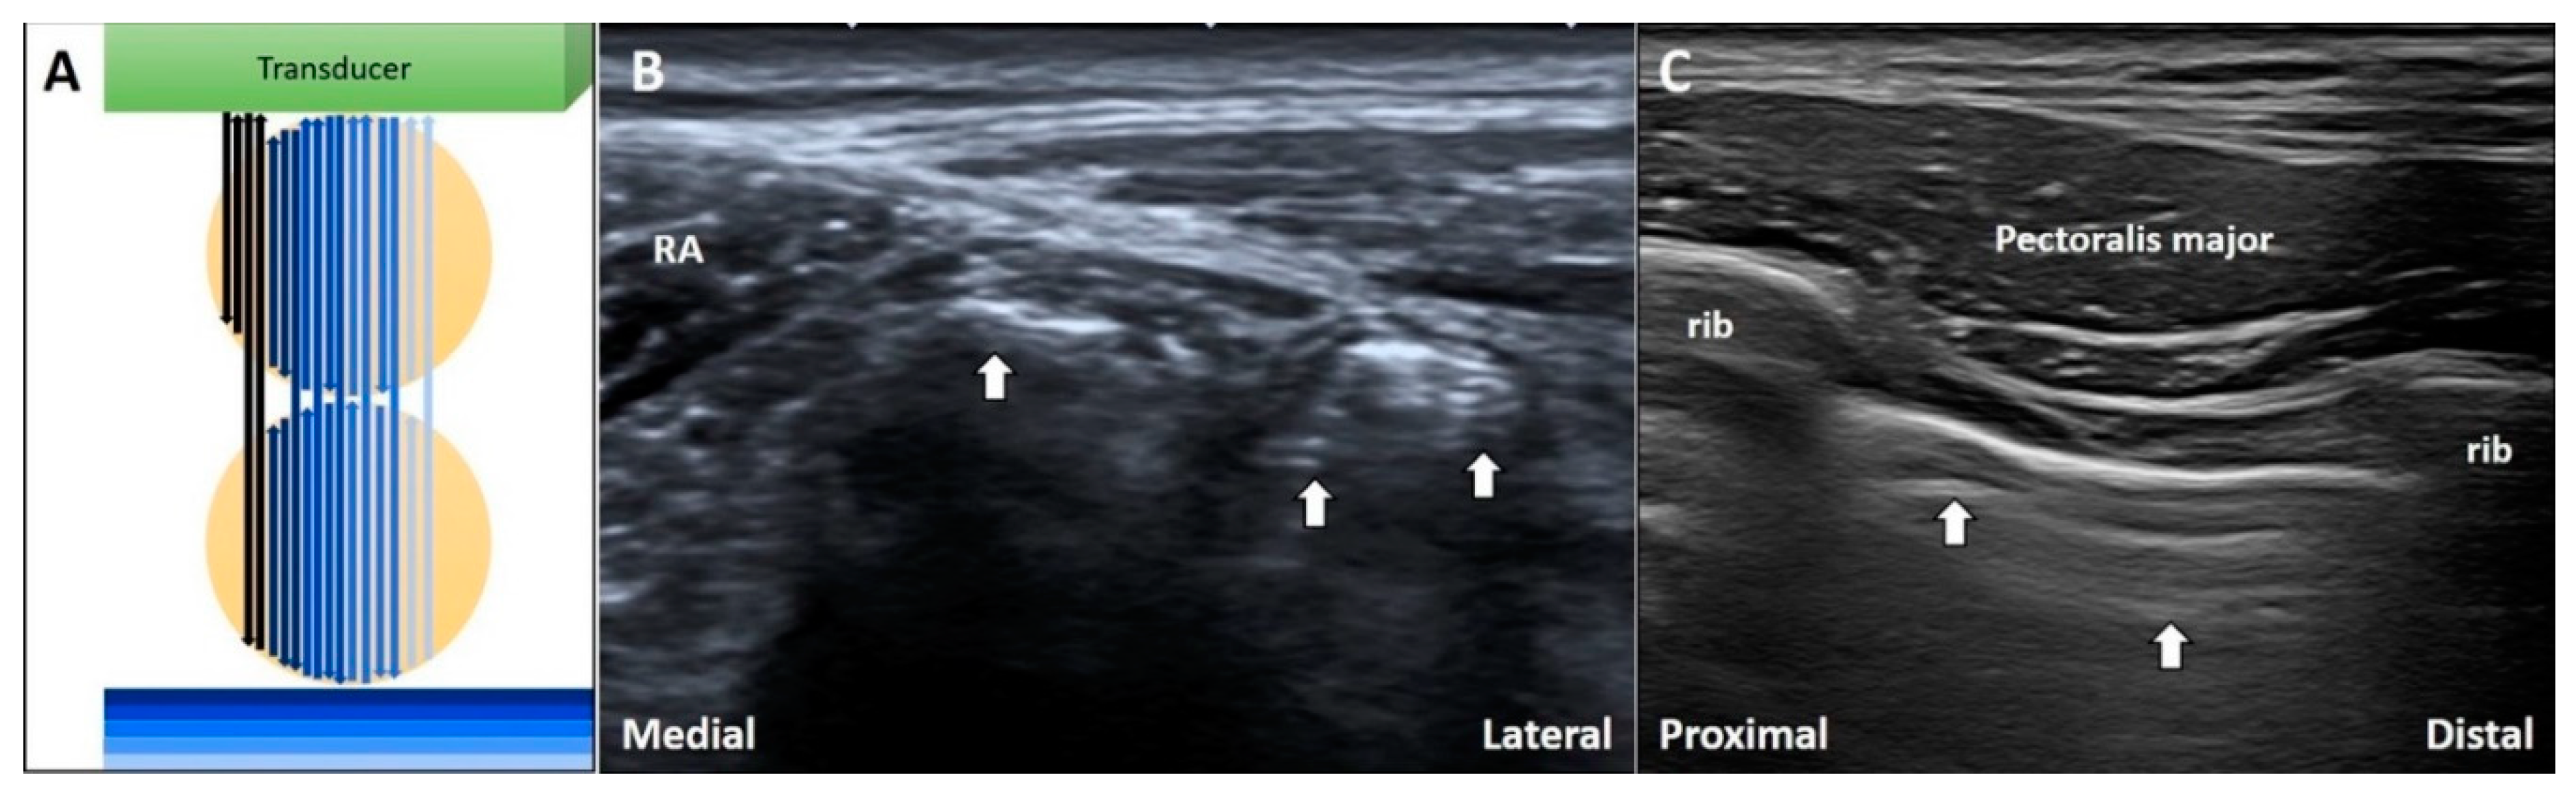

When the US beam passes through air bubbles, sound waves resonate within the bubbles, emitting continuous waves back to the transducer. This is known as the ring down artifact. The US streaks decay as they move away from the target (Figure 8A) [25].

Figure 8.

The schematic drawing illustrates the ring-down artifacts when the US waves pass through the air bubbles (A). During imaging for inguinal hernia, the ring-down artifacts can be seen in the bowels (B). During intercostal block, the ring-down artifacts can be visualized deep to the pleura (C). White arrow: ring-down artifacts. RA: rectus abdominis. Black and blue arrow: the projected and reflected US beams.

3.4.2. Clinical Examples

During investigation of an inguinal hernia, ring down artifacts are commonly observed in the bowel due to intra-lumen gas (Figure 8B). In cases of subcutaneous infections, the ring down artifact can develop through accumulation of gas formed by anaerobic bacteria. Further, during the performance of intercostal nerve block [26] or injections in trigger points of the rhomboid muscle, medical professionals should be cautious so as not to puncture the pleura that also present ring down artifacts (Figure 8C).